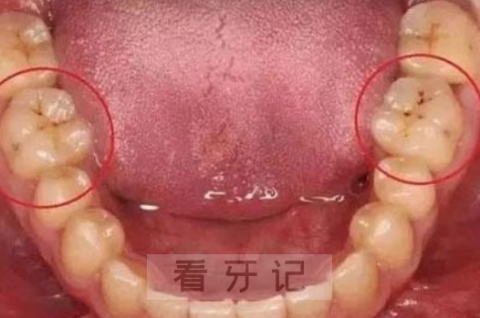

2、当我们发现自己的牙齿表面形成黑线,初步形成蛀牙

黑点没有重视,慢慢的往四周蔓延,就形成了一条黑线。这时你可能还是感觉不到疼痛,所以还是没有重视,等等再说。